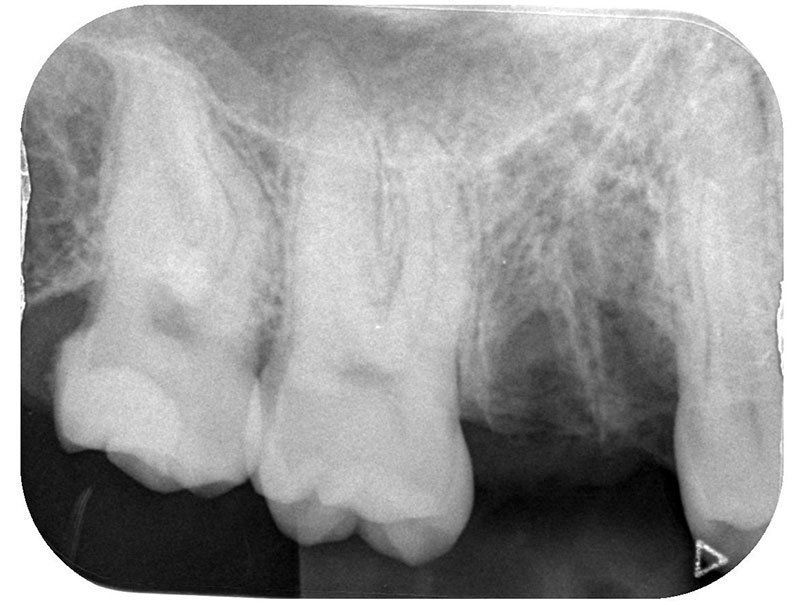

右下6の状態としては虫歯が進行していて、保存不可の状態でした。患者様との相談の結果、インプラント治療を行うことになりました。

残根抜歯とPRGFを使用した抜歯窩の保存